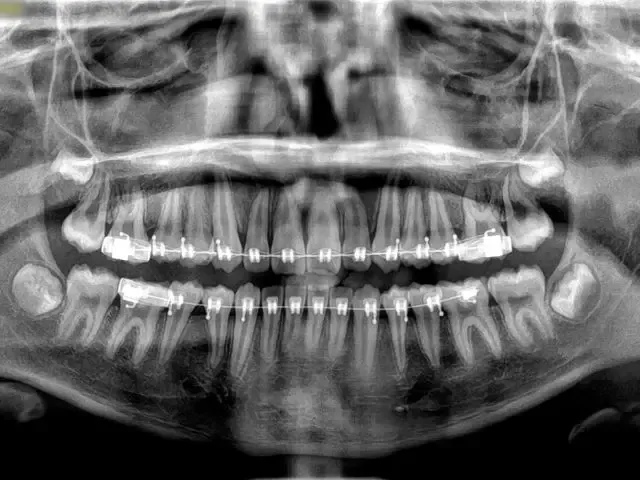

Equipos de radiografías y Scanner 3D

Debemos evaluar a fondo tus dientes y la posición de tus maxilares respecto a tu cráneo. Lo realizas en nuestra Clínica y es por orden de llegada.

El Ortodoncista revisará tus radiografías y te dirá que tipo de tratamiento debes seguir. Él

planificará el movimiento de tus piezas dentales.

Sala Imagenología Digital Rxs Panorámicas, Escáner, Teleradiografías, bite wing, periapicales